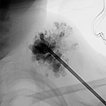

Sclerotherapy was performed in view of the rapid growth in size and recurrent painful thrombophlebitis. The contrast injection via an inserted puncture needle depicted here shows extensive contrasting of the venous malformation, thus good conditions for successful sclerotherapy.

Digital subtraction angiography after contrast injection via the same needle also shows very clearly the almost complete filling of the venous malformation from this needle position. Only small, very thin-lumen communicating veins present themselves. Therefore, a large part of the venous malformation can be sclerosed from this needle position.

In the fluoroscopic control (lateral plane) after injection of 8 ml of polidocanol foam (3%, 1 : 4 foamed in air), the entire venous malformation is filled with the non-contrasting foam. The previously contained contrast medium is almost completely displaced by the sclerosing foam. Thus there is a good chance that the lesion will be very largely closed by the procedure.